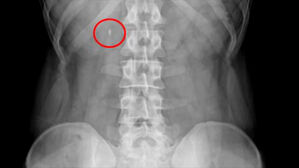

옆구리 찌릿! 혹시 요로결석?…AI가 CT 영상 분석해 찾아낸다 ▲ 요로결석 엑스레이 인공지능이 의료 분야에 빠르게 스며들고 있습니다. 최근에는 컴퓨터단층촬영 영상만으로 요로결석 진단을 돕는 AI … SBS 2025.05.20 06:08